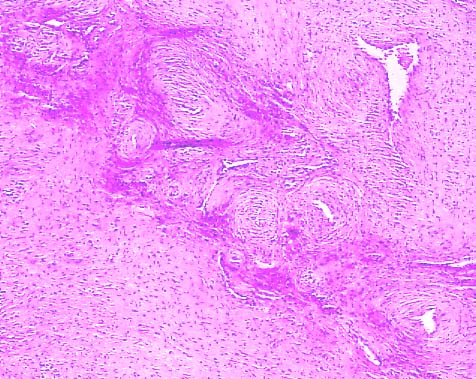

Ангиомиома представляет собой доброкачественное новообразование, которое может возникать в различных частях тела. Эта опухоль характеризуется медленным ростом и крайне редко трансформируется в злокачественную форму. Она состоит из жировой и мышечной тканей, а также измененных кровеносных сосудов и эпителиальных клеток. Также ангиомиома известна под названиями сосудистая лейомиома и ангиомиолипома.

- ангиомиома — это новообразование, у которого сильно развита сеть кровеносных сосудов.

В зависимости от того какой сосуд преобладает в структуре новообразования ангиомиома бывает:

- венозная;

- артериальная;

- смешанная;

- малодифференцированная.